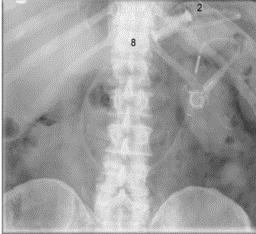

El síndrome del remanente gástrico es una secuela rara de obstrucción, pero el hecho de no reconocer su aparición puede provocar perforación, peritonitis y, posteriormente, la muerte. Las características incluyen dolor epigástrico, distensión, hipo, distensión y timpánica en la parte superior del abdomen, disnea o taquicardia. Una radiografía simple de abdomen puede mostrar una burbuja de aire gástrico y el diagnóstico se puede confirmar en la tomografía computarizada con contraste oral.

A pesar de los beneficios bien documentados de la cirugía laparoscópica, su uso en el bypass gástrico en Y de Roux se asocia con un aumento en la formación de hernias internas. Se cree que esto se debe a menos adherencias que se desarrollan después de un abordaje laparoscópico. Los sitios de herniación potencial incluyen (a) el defecto en el mesocolon transversal si la extremidad de Roux se coloca en una posición retrocólica (mesocólica)

(b) el espacio entre el mesenterio de la extremidad de Roux y el mesocolon transversal (Peterson’s hernia)

(c) el defecto mesentérico en el sitio de la yeyuno-yeyunostomía (ver Fig. 9).